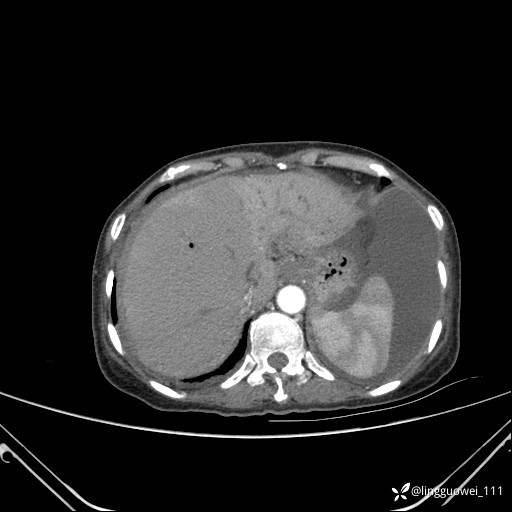

病例女,65岁,门诊行胃肠镜检查后,说腹胀入院检查,CT能发现病因吗?已公布结果

主诉:门诊行胃肠镜检查后,诉腹胀,入院检查,肝有病变吗?腹膜及腹腔的表现有特征性吗?

延迟期: